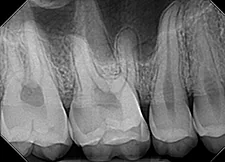

Image Quality

Ultimately, quality is the most important factor in a dental X-ray sensor. A sharp image ensures a proper diagnosis for patients. The Dream Sensor produces easy-to-view, crisp images that work with almost any existing dental software. The results of the direct comparison of DentiMax vs. Dexis are clear.

![]() X-ray taken with the DentiMax sensor shown in Sidexis 4™ software | ![]() X-ray taken with the Dexis™ sensor |